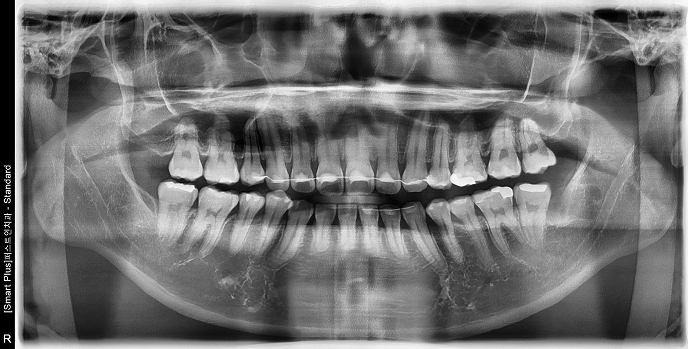

• 30대 여성 | #38 사랑니발치 | 치료기간 당일

Before 2025.03.06

After 2025.03.06